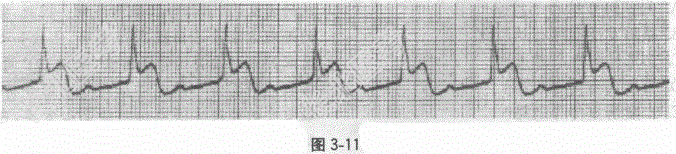

- [材料题] 男性患者,68岁。突发胸骨后剧烈疼痛,持续3小时,伴大汗,急诊入院。有吸烟、饮酒史。心电图见图。

- 单项选择题1.心电图诊断为

A、急性下壁心梗,2︰1房室传导阻滞

B、急性下壁心梗,一度房室传导阻滞

C、急性下壁心梗,二度Ⅰ型房室传导阻滞

D、急性下壁心梗,二度Ⅱ型房室传导阻滞

E、急性下壁心梗,三度房室传导阻滞